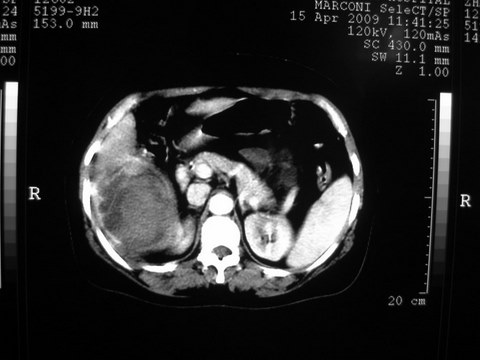

患者 女 51岁 两天前感觉上腹疼,无明显诱因,b超示肝右叶囊实性占位,边缘清楚,其内回声不均匀,ct增强如图,大家看看是什么 ,病人一年前及两月前b超检查只是提示胆囊炎

外院术后,证实肝癌合并出血

特点:1,病灶发展迅速,(2月前正常)[br] 2,囊实性,且并边界清晰光滑,呈右后叶赘生性。囊性区无强化,实性部分较多轻度强化,边界欠清。考虑囊腺癌或囊腺瘤。

出病理 中分化肝细胞癌合并出血